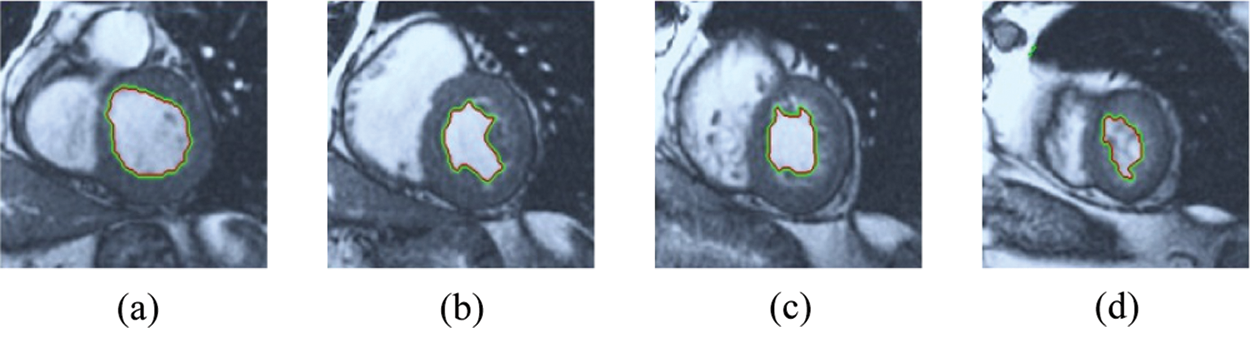

The BRW, HSRW, and ERW medical imaging segmentation schemes are executed on MATLAB, and examined on a short-axis of 3D multi-slices CMRI dataset [27]. Several segmentation performance metrics are utilized such as Dice Metric (DM), the Haussdorff distance (HS), and the Peak signal to noise ratio (PSNR). The BRW, HSRW, and ERW segmentation schemes are executed on a short-axis of 3D multi-slices CMRI datasets. The same multilayer CMRI dataset is segmented using various random walk methods. The presented results were obtained through using BRW, HSRW and ERW methods on five different groups of patients; each group contains 25 subject of multilayer CMR dataset. Experimental results illustrate that the BRW method can achieve a good segmentation of the LV cavity. The results of the HSRW algorithm have very comparable similarities to BRW, but with a slightly less efficiency and a much higher execution rate. Pre-calculations reduce the performance online time in offline mode. The average time of HSRW equals to 0.09 seconds for each slide. Raising the rate of K will improve the comparison and makes the process of segmentation more precise, but also reduces the execution time. The ERW technique results illustrate that this method has the greatest efficiency of segmentation. Figs. 5 to 7 show the resulting images of the BRW segmentation method on five sets of sample data. HSRW with pre-calculation segmentation method is applied on the same sets of sample data and illustrated in Figs. 8 to 10. Figs. 11–13 show the high efficiency segmentation using the ERW method with an earlier model for the same sets of sample data. The results of the Random Walk segmentation overcame the potential restrictions of the prior art CMR methods. The performance of segmentation is fast compared to segmentation methods based on edge and region. BRW precedes into account the properties of regions and edges, as shown in Figs. 5–7. Looking at the image as a graph, the technique makes it possible to integrate pixel relations with neighboring pixels. As a result, segmentation produces good quality BRW technique sections when their qualitative accuracy is compared to the ground truth, and this is also evident from the Tab. 1 measurements in the diastolic and systolic phases in Tab. 2 as well as in the complete cardiac cycle noticed. Figs. 8–10 illustrate the HSRW results. There are no dissimilarities observed in furthermost cases of CMR slides in the figures, but the correspondence measurements of the DM, PSNR and HS coefficients present that the results of the HSRW technique are worse than those of the BRW method. This presents that HSRW is an effective estimation of the random walk influence as mentioned in Tab. 1 and throughout the cardiac cycle in Tab. 2. The values of PSNR and DM are lower, whereas HS is higher than the BRW method, but with slight dissimilarities between HSRW and BRW methods throughout the blood circulation. The impact of execution eigenvectors pre-calculations is perfect when the execution time is faster than the BRW method and, in fact, more efficient than other segmentation method for LV heart segmentation. With the identical dataset, the ERW method shows a significant enhancement in efficiency, as presented in Figs. 11–13. From the scores, we can see that the segmentation is smoother and cleaner. The ERW method considers boundaries and areas, such as BRW, using the relations between adjacent pixels in the image. It also considers the additional regional advantage by including the assumptions that affect the results of the segmentation. Mean segmentation quality measurements are computed from the segmented images using correspondence measurements for instance DM, HS, and PSNR and verified for each method in the diastolic and systolic stages as presented in Tab. 1. Based on results, it can be determined that methods of random walk are enhanced in diastolic diagnosis and that their outcomes in the systolic stage are also of good efficiency. The results of the random walk segmentation methods in the complete blood circulation are shown in Tab. 2. The cardiac cycle similarity amounts indicate that DM and PSNR capacities of ERW are improved than the corresponding capacities in the case of the HSRW and BRW approaches; however, the HS measurements are lower than the equivalent measurements, as illustrated in Tab. 2. This designates that the ERW technique is the furthermost accurate segmentation technique among all the approaches stated above. The ERW technique has the uppermost value of PSNR, and the HSRW method has the lowermost value that denotes the uppermost speed in segmentation process.

Figure 11: ERW results for the first samples set

Figure 12: ERW results for the second samples set

Figure 13: ERW results for the third samples set